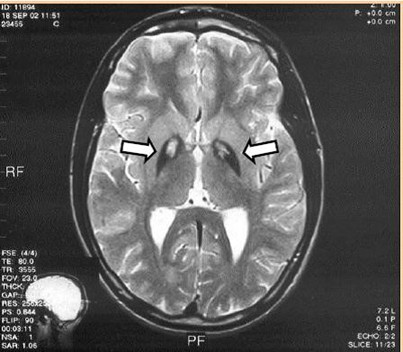

Objaw tzw. „tygrysiego oka” gałki bladej w badaniu MR mózgu w obrazach T2 zależnych jest typowy dla: